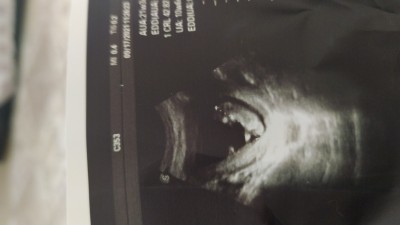

10.haftalık gebeyım doktora sormadım bır bakarmısınız kızmı erkekmi bn anlayamadım

Gebelik haftası 10

Rabbim anneli babalı büyütsün güzellik burada çok küçük  bu yüzden cinsiyet beyli olmaz 7 haftada kalp atışı duyulur sabır inşallah sağlıklı sıhhatli gelir dünyaya Allah gönlüne göre versin

Erkek gibi geldi içimden canım normalde cinsiyet için çok erken erkekte kızda aynı oluyor net cinsiyet tahmini16 hafta yapılıyor rabbim gönlüne göre versin inşallah

doktora sorsanda daha söylemezdi çünkü belli değil organı bile oluşmaya başlamamış haftası çok küçük annesi :) rabbim gönlüne göre versin

10 haftalik zaten doktorda  goremez canim  12.haftada ultrasonda gorulebilecek ladar oluyor